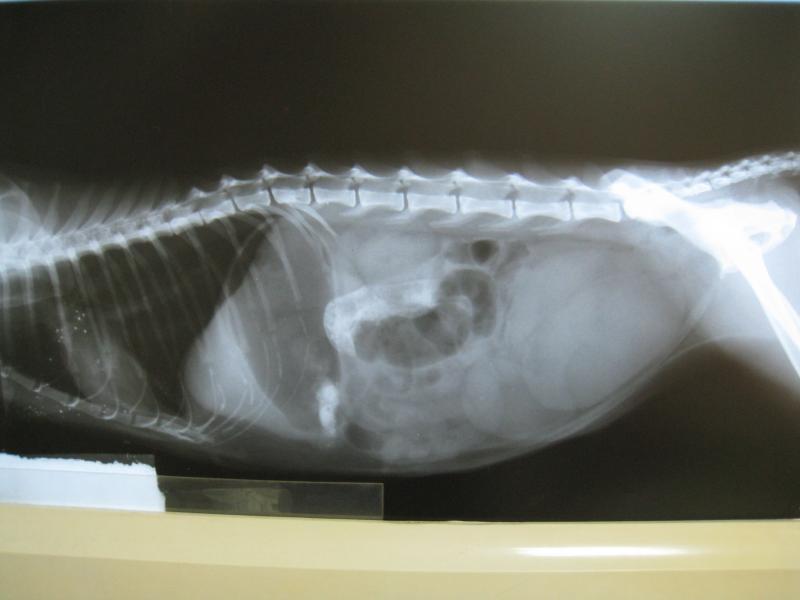

經過檢查發現腸道內有異物,

但三天後,X光檢查還是發現異物存在,

在評估後,因為此時貓咪的呼吸道感染已經改善7成的,

但是胰臟指數還是偏高,擔心對生命造成威脅,因此決定開刀將異物取出。

手術後發現是含有許多砂石的糞泥堵住的腸腔,